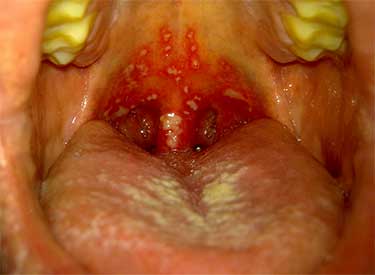

- Фолликулярная ангина сопровождается воспалением фолликулов, расположенных в тканях миндалин. Как правило, первым симптомом является повышение температуры, першение и боль в горле. Слизистые оболочки краснеют и отекают, что значительно осложняет процесс глотания. При осмотре можно заметить мелкие прыщики на миндалинах — это увеличенные фолликулы, внутри которых скапливаются гнойные массы. В некоторых случаях небольшие расположенные близко гнойнички сливаются между собой, образуя крупный абсцесс. Нагноившиеся фолликулы периодически вскрываются. При правильно проведенном лечении недуг заканчивается полным выздоровлением (терапия, как правило, длится 7-10 дней).

- Лакунарная форма заболевания также считается весьма распространенной. В данном случае на фоне воспалительного процесса слизистые выделения накапливаются не в фолликулах, а в извилистых углублениях гланд (лакунах). Миндалины увеличиваются в размерах и приобретают бугристую структуру. Нередко при осмотре горла можно заметить образованные на гландах крупные гнойники белого или желтого цвета. Довольно часто данная форма недуга протекает с осложнениями, требует агрессивной антибактериальной терапии и госпитализации. При отсутствии лечения (особенно если иммунная система пациента ослаблена) ангина может осложниться образованием абсцесса, развитием менингита и даже сепсиса.

- Как свидетельствует статистика, в большинстве случаев в роли возбудителей выступают бактерии, в частности, стрептококки и стафилококки. Тем не менее воспалительный процесс может быть результатом активности вирусов (в частности, герпеса, аденовируса или энтеровируса). Такая форма ангины сопровождается сильным покраснением и отеком гланд, образованием мелких пузырчатых высыпаний на слизистых оболочках горла и неба. Нередко после вскрытия прыщиков на их месте образуются болезненные язвочки.